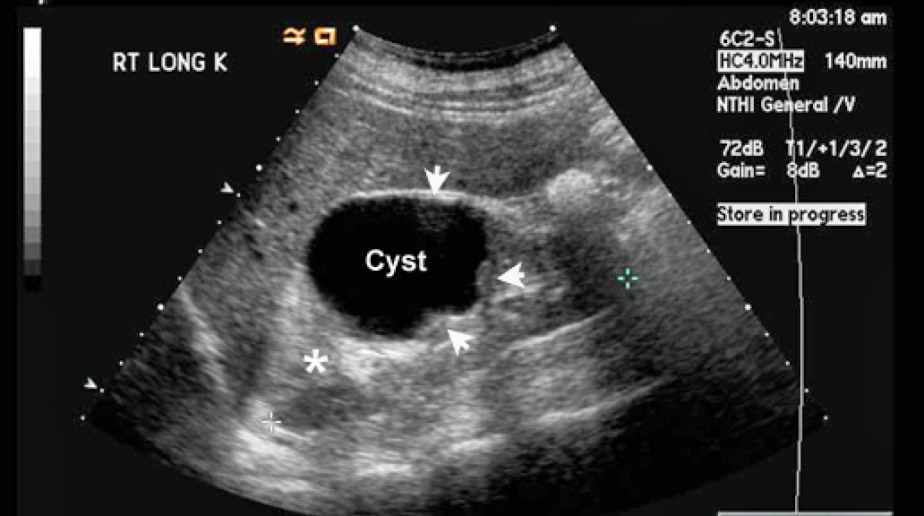

Normal Kidney Ultrasound What Do Red Spots Mean On Ultrasound Red and blue colors represent the movement of the blood. They are part of a doppler ultrasound used to assess blood flow direction. What does red or blue mean on an ultrasound? If you're 12 weeks along in the pregnancy, you may be able to make out your baby's head, and if you're 20 weeks along, you may even see. What Do Red Spots Mean On Ultrasound.